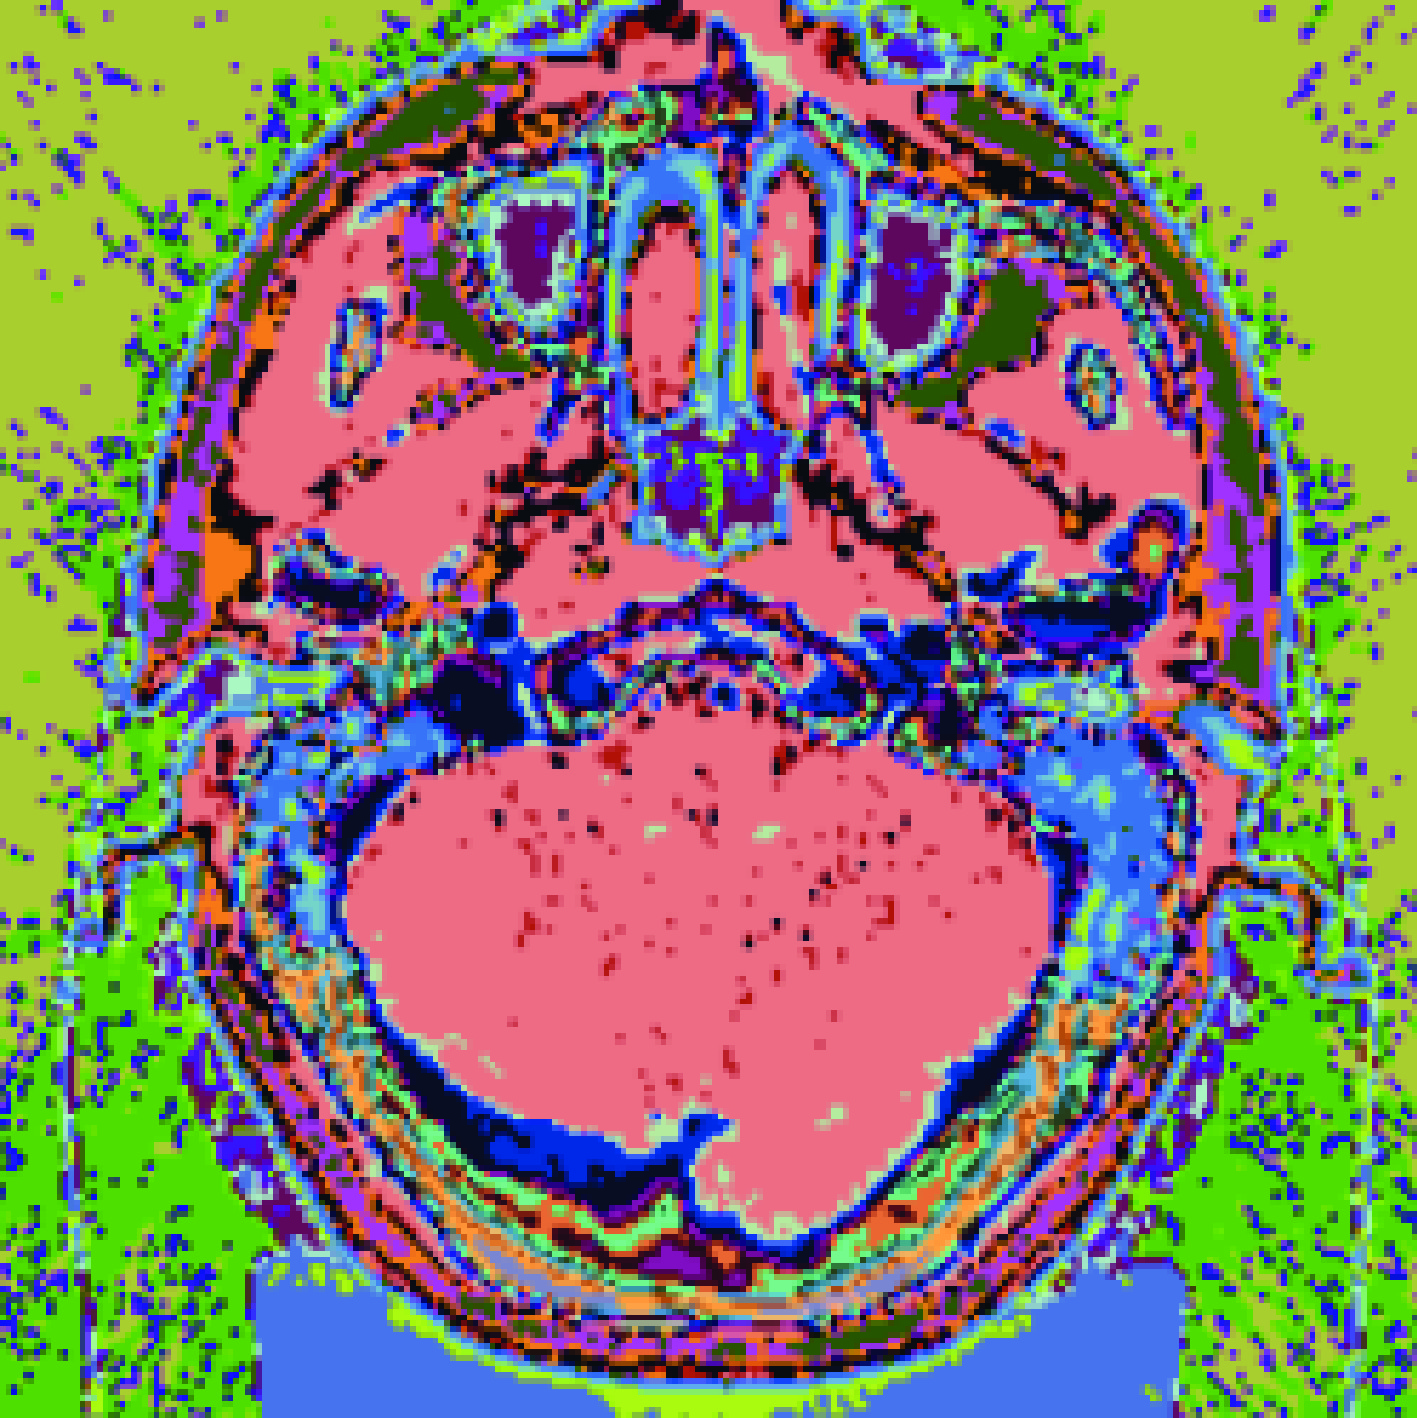

Within the medical-image platform MeVisLab, we complete DICOM registration, target delineation, and RTStruct/RTDose interfaces; the open-source Monte Carlo code OpenMC is used as the engine to execute neutron-transport simulation, realizing HU-to-material mapping and variable-mesh calculation.

Validation with clinical CT data simulated by the system shows that at a depth of 22 cm in the tumour target, the boron dose accounts for 80.9% of the total dose.